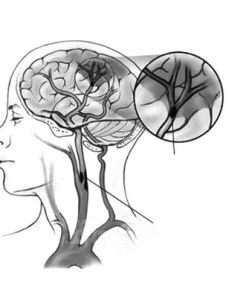

先天性腦血管畸形先天性腦血管畸形亦稱血管瘤,非真性腫瘤,系先天性腦血管發育異常,臨床上有多種類型,其中以動靜脈畸形多見,根據畸形血管團直徑的大小,臨床分為大、中、小型病變。本病多見於男性,青年多見。臨床表現以畸形血管破裂出血為最常見症狀,部分病人以癲癇為首發症狀;由於“盜血”現象,局限性腦缺血可致腦萎縮,智力減退、精神不正常可存在。如出血嚴重,出現腦疝,如不及時救治,常可致死。本病治療方法較多,其中手術切除病源最為理想。血管內介入治療與γ-刀治療是一種全新治療方法。

1.一般症狀:搏動性頭痛,位於病側,可伴顱內血管雜音。2.出血:常為首發症狀,表現為蛛網膜下腔出血或腦內血腫。3.癲癇:可為首發症狀或見於出血後,多為全身性發作或局限性發作,局限性發作有定位意義。4.局源症狀:幕上病變者可有精神異常,偏癱、失語、失讀、失算等。幕下者多見眩暈、復視、眼顫及步態不穩等。5、該病兒童時期在外表就可以看出一些基本症狀:有些人在3、5歲時表現出不能走長路,走0.5公里左右的路小孩就出現疲軟,需要原地休息;讀書時,在大腦發育的前階段,特別聰明,成績很好,在大腦需要大量供血的階段,因為供血不足,大腦不能正常發育,所以有此病的學生,一般在進入國中階段開始成績下降。該病的最大特徵就是沒有任何可以明顯感知到的症狀,要到發病後才可以知道是該病,但是為時已晚,錯過了最佳治療時機。建議有上述兩個特徵的小孩到醫院進行腦造影進行診斷。診斷依據

1.青少年患者,有頭痛、癲癇和蛛網腔下腔出血史。2.臨床表現有急性顱內自發出血、或癲癇發作、或明顯局源體徵者。3.頭部CT:平掃病變常為低密度、周圍亦有低密度,若腦內出血可見高密度,增強後血管區呈高密度,有時可見供血動脈和引流靜脈。4.頭部MRI:優於CT,不僅能顯示畸形血管及其周圍腦組織,還可區別出血與鈣化。MRI血管造影相可提高畸形血管團的診斷率。5.腦血管造影:最可靠、最重要的診斷方法,動脈期可見血管團、供血動脈及早期顯現的引流靜脈。

1.頭顱平片顯示顱內板受侵蝕及腦膜中動脈迂曲變寬,提示畸形血管可能。2.頭部CT可發現血腫及提供畸形血管的可能性。3.頭部磁共振:優於CT,不僅能顯示畸形血管及其與周圍腦組織的關係,還可區別出血與鈣化。4.腦血管造影是本病最可靠和主要的診斷方法,並能行血管內介入治療。